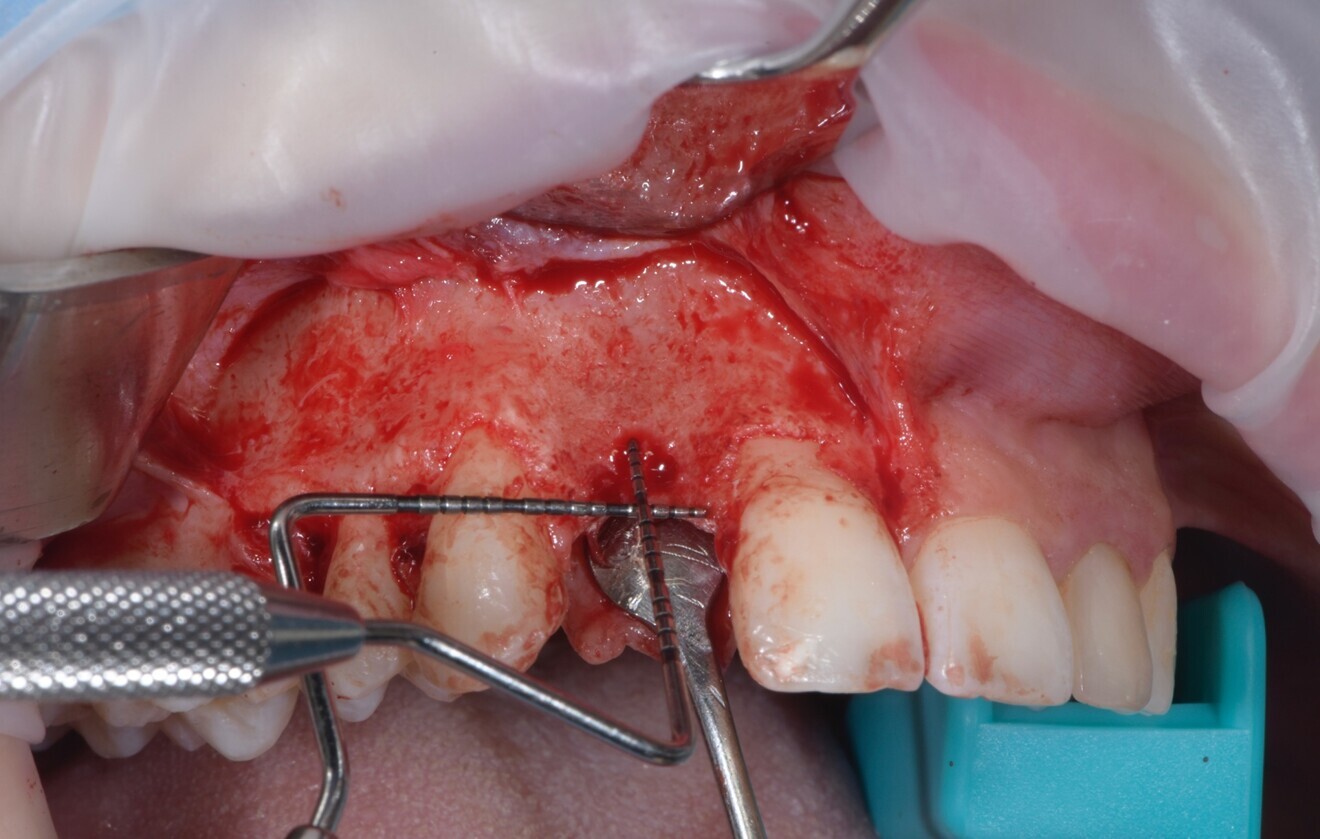

Fig. 3: Atraumatic implant removal using reverse technique.

At the initial visit, digital impressions were obtained using the Medit i700 scanner. Periapical radiographs and standardised intra-oral and extra-oral photographs were also acquired. A virtual diagnostic wax-up was generated to guide treatment planning. On the day of surgery, local anaesthesia was administered, and the implant was atraumatically removed using the reverse torque explantation technique. The surgical site was debrided and cleaned, and Type I collagen was applied to the socket (Fig. 3).

Anaesthesia was delivered using 4% articaine with 1:100,000 adrenaline (Ubistesin, 3M ESPE). A crestal incision through the keratinised mucosa was made using a No.15c blade, and a full-thickness flap was elevated. Vertical releasing incisions were placed two teeth away, both mesially and distally (Fig. 4).